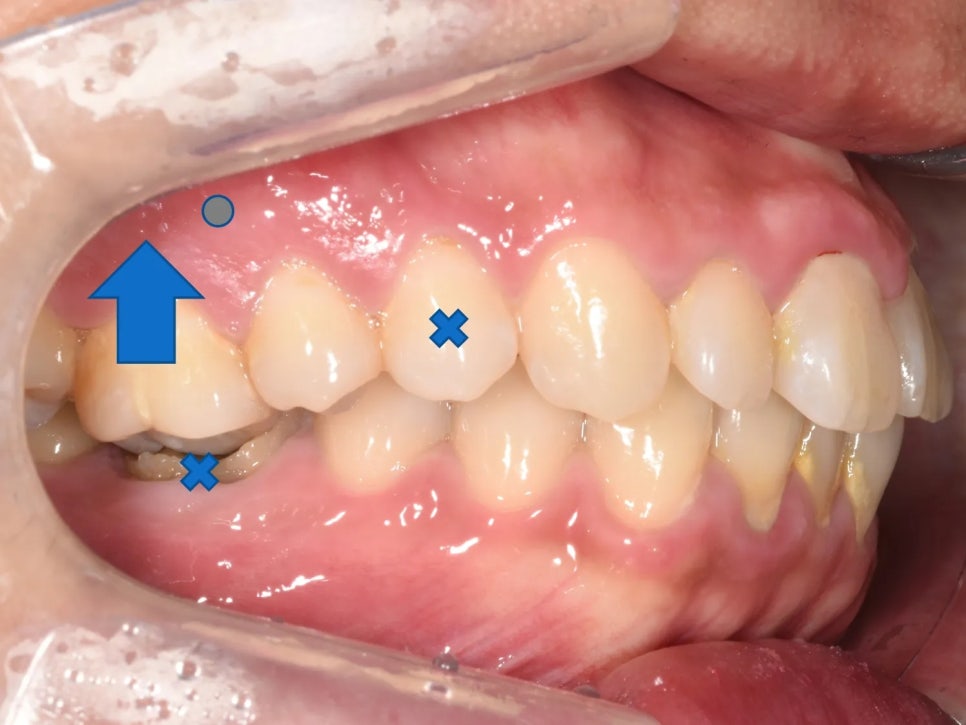

가장 먼저 눈에 띈 문제는 오른쪽 위 첫째 어금니였습니다. 이 치아가 아래쪽 치아와 제대로 물리지 않다 보니, 점점 아래로 내려와 있었던 것입니다. 이런 현상을 '정출'이라고 합니다.

문제는 이 내려온 어금니가 교합 간섭을 일으킨다는 점이었습니다. 입을 다물 때 이 치아가 먼저 부딪히니까(간섭), 환자분은 자연스럽게 아래턱을 왼쪽으로 틀어서 물 수밖에 없었습니다. 이런 것을 '하악 편위'라고 하는데, 다행히 턱관절 자체에 큰 이상은 없었지만 이런 상태가 오래 계속되면 턱관절 장애로 이어질 위험까지 있습니다.

추가적으로, 아래쪽 오른쪽 첫째 어금니에는 심한 충치가 있었고, 반대쪽(왼쪽) 아래 두 번째 작은어금니는 이미 빠진 상태(결손)였습니다. 충치로 인해 치아 높이가 낮아지면서 위 어금니가 더 빨리 정출되었고, 결손 부위에서는 인접 치아가 빈 공간 쪽으로 쓰러져 있었습니다. 아래 사진을 보시면 이 모든 이유 때문에 결국 환자분이 아래턱을 틀어 물고 있는 것도 확인해보실 수 있습니다.

아래턱을 약간 왼쪽(→)으로 물고 있는 것이 보이십니까?

옆에서 본 치료 계획 – 발치 위치, 어금니 함입 방향, 스크류 위치가 회색으로 표시되어 있음.